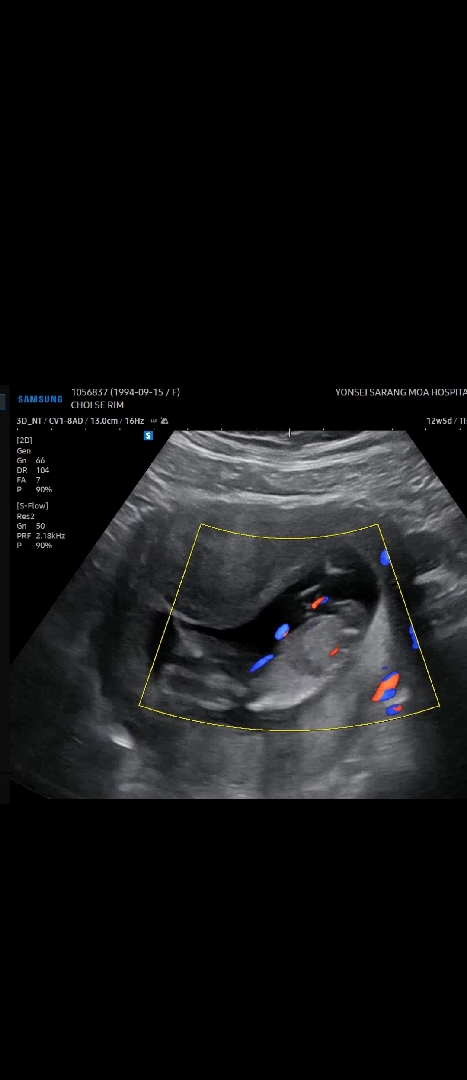

12주 5일인데 각도법 부탁드립니다!

오늘 1차 기형아 검사했는데 애기가 웅크리고 있어서 잘 안보이고 말씀 안해주시네요 ㅠ 혹시 각도법으로 알수 있을까요??